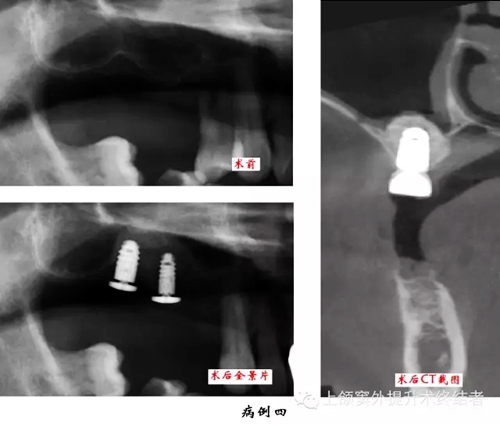

術(shù)前檢查口腔內(nèi)情況,主要包括骨和粘膜的狀況。拍攝曲體層片,測(cè)量并按其放大率計(jì)數(shù)上頜竇底至牙槽嵴頂?shù)木嚯x,檢查上頜竇形態(tài)和密度,排除無(wú)癥狀的上頜竇慢性炎癥或囊腫等。觀察竇內(nèi)有無(wú)上頜竇橫隔,位置是否影響手術(shù)操作,如有影響則需調(diào)整開(kāi)窗位置。拍攝直線體層片和上頜竇矢狀面體層片可以顯示上頜竇底斷面或矢狀面的現(xiàn)狀,但以上圖像都有一定程度的放大失真。如有條件采用三維螺旋CT進(jìn)行掃描可以準(zhǔn)確測(cè)量上頜竇底至牙槽嵴頂?shù)膶?shí)際距離,觀察上頜骨形態(tài),分析術(shù)區(qū)條件和檢查上頜竇健康狀況,以利于進(jìn)行術(shù)前診斷和制定治療計(jì)劃。上頜竇底提升同期種植術(shù)前應(yīng)制作手術(shù)模板。